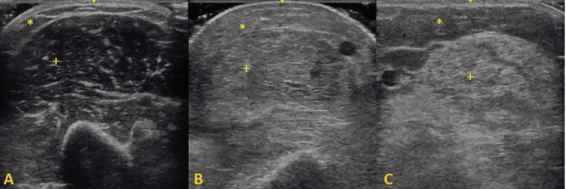

When the muscle becomes abnormal, various changes can be seen structurally. With muscle conditions that cause fat replacement and fibrosis, the muscle turns whiter as a result of an increase in the number of reflecting surfaces within the muscle [9]. Depending on the severity, the underlying bone echo can become reduced or absent. This observation was first described by Heckmatt, et al. in 1980 [9], who later proposed a four-point scale to classify the intensity of echo reflected from the muscle which is currently known as the 'Heckmatt criteria': grade 1 -normal; grade 2 - increase in muscle echo while bone is still distinct; grade 3 - marked increase in muscle echo and reduced bone echo; grade 4 - very strong muscle echo and complete loss of bone echo [10]. Furthermore, changes in muscle thickness can also occur in affected muscles and can be measured using a digital caliper (Figure 1).

Figure 1: Representative ultrasound images of the biceps brachii muscle: + - muscle tissue, * - subcutaneous fat. A) Normal muscle: hypoechogenic muscle tissue with speckled pattern of echogenic reflections from perimysial connective tissue; B) Dermatomyositis: an increase in muscle echo intensity and increased echogenicity of subcutaneous fat; C) Inclusion Body Myositis: A marked increase of echo intensity due to fatty replacement of muscle tissue. View Figure 1